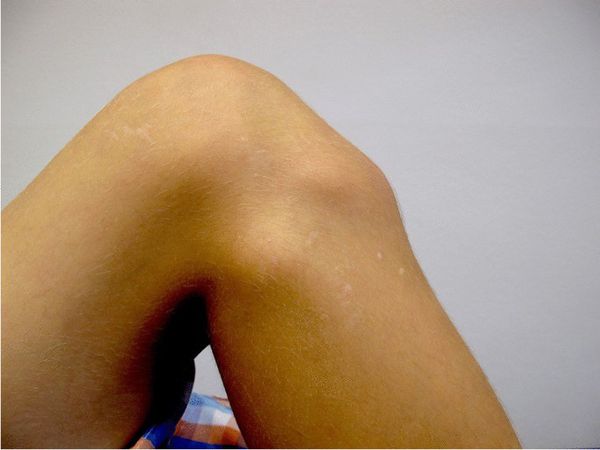

При частых сгибаниях коленного сустава в месте бугристисти большеберцовой кости может появиться твёрдый на ощупь бугорок. Кроме выпячивания пациента ничего не беспокоит.

![Бугорок под коленом [18]](/pimg3/osteoxondropatiya-bugristosti-bolshebert-E72429.jpeg)

Болезнь Шляттера приводит к перестройке бугристости, нестабильности коленного сустава и напряжению мягких тканей ног, из-за чего у людей возникает боль под коленным суставом уже во взрослом возрасте.